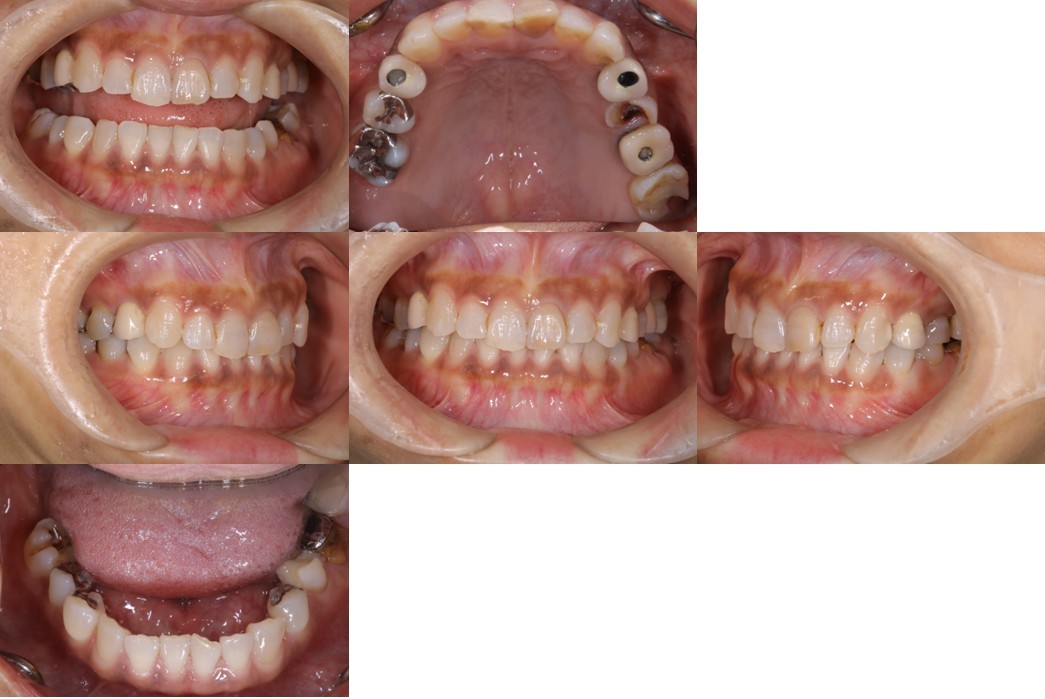

「生活歯髄保存療法」症例 ●初診時年齢30代 女性

機能的な咀嚼障害を主訴に来院(図18・19)。咬合状態は不安定で、矯正治療を含めた全顎的な治療が必要と診断した。治療計画では右上4・6、左上4・6、左下6部に、それぞれインプラント治療を計画した。右上5、左上5は、隣在歯が近遠ともインプラント治療になるため感覚受容器が乏しくなることが予測されるため、歯髄の有無が大きく影響されやすい環境と判断した。

(図18)初診時の口腔内写真

前歯部には叢生が存在しアンテリアガイダンスが失われた状態

上顎の臼歯の咬合面形態が大きく崩壊し、バーティカルストップを失ったことによる咬合の不安定が予測される